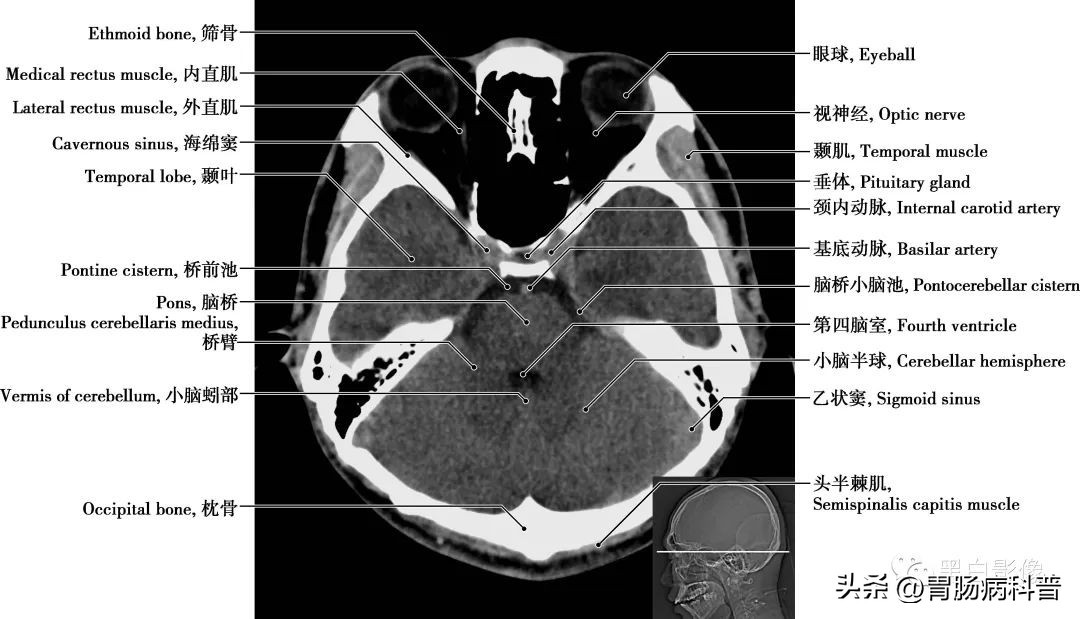

图1-1-13 经海绵窦轴位切面

垂体 位于下丘脑的腹侧,为一卵圆形小体。分为腺垂体,包括远侧部、结节部和中间部;神经垂体由神经部和漏斗部组成,神经垂体较小,由第三脑室底向下突出形成。垂体分泌多种激素,如生长激素、促甲状腺激素、促肾上腺皮质激素、促性腺素、催产素、催乳素、黑色细胞刺激素等,还能够贮藏下丘脑分泌的抗利尿激素